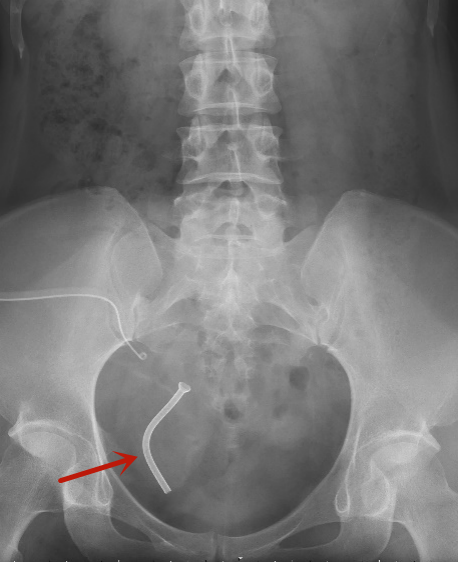

移植肾输尿管狭窄患者为一名30岁女性。外院行异体肾移植术2个月后,出现输尿管膀胱吻合口重度狭窄继发肾积水,肌酐增高到220ummol/L,接近正常最高值的3倍。先后两次行输尿管扩张等手术,术后均再次出现输尿管狭窄、肾积水,严重影响移植肾功能,只能依靠移植肾造瘘管维持生活工作。

对于此类输尿管严重狭窄的患者,再次行开放的输尿管膀胱吻合术仍然有较高的失败率和再狭窄率,且常规输尿管支架管的留置时限较短,需定期更换,容易继发感染和结石,对本就是移植肾的功能影响较大,为了减少多次支架植入为患者带来的创伤和不便,更好地在支撑、扩张输尿管的同时引流尿液,保护肾功能,泌尿外科团队决定为患者植入新型金属支架。

红色箭头处为支架植入位置

“要想顺利完成金属支架植入,术前、术中精准测量狭窄段长度,测算需要的金属支架型号和适合的留置位置非常重要。”泌尿外科主任李建兴说。为此,他多次组织病例讨论和文献复习,规划每一个手术要点和注意事项。术前,团队采用CTU、造影等检查预先确定狭窄段位置和长度,术中,泌尿外科副主任胡卫国与主治医师苏博兴合作主刀,使用X射线透视与内镜引导相结合,通过经皮肾镜和逆行输尿管镜双镜联合成功“打通”输尿管狭窄,顺利留置金属支架。术后随访1月,患者顺利拔除肾造瘘管,复查肾积水消失,肾功能肌酐水平降至正常,恢复正常生活。